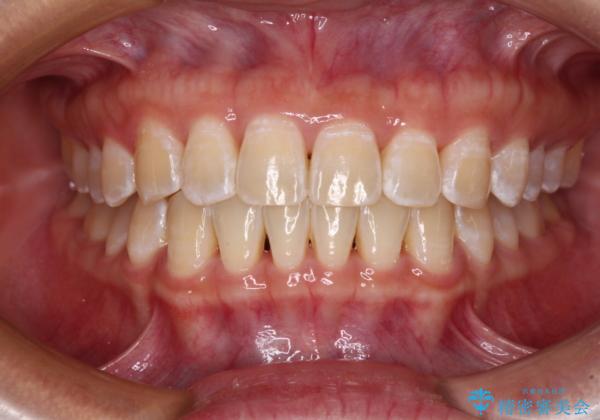

前歯の隙間と上下正中のズレを解消

- 上下前歯隙間と正中のズレを改善したいとのことで来院された患者様です。

自己管理を減らしたいとのことで、ワイヤー装置による矯正治療を行うこととしました。

正中がなかなか合わずに、2年近くの治療期間を要しました。